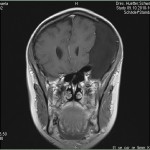

Ich stell euch hier noch eine kleine Galerie rein mit den neuesten Bildern. Ich denke es ist unübersehbar, dass das Ding gewachsen ist, außerdem mir meine komplette Hirnmittelline verschiebt und immer mehr Rücklagerung bekommt und Richtung Hirnsteuerungszentrum drückt. Meine häufiger auftretenden Stürze und Koordinationsprobleme werden also in naher Zukunft sicherlich nicht weniger werden und mein Doc und ich werden uns wohl auch zeitnah über eine weitere Klinik und eine mögliche weitere OP unterhalten müssen.